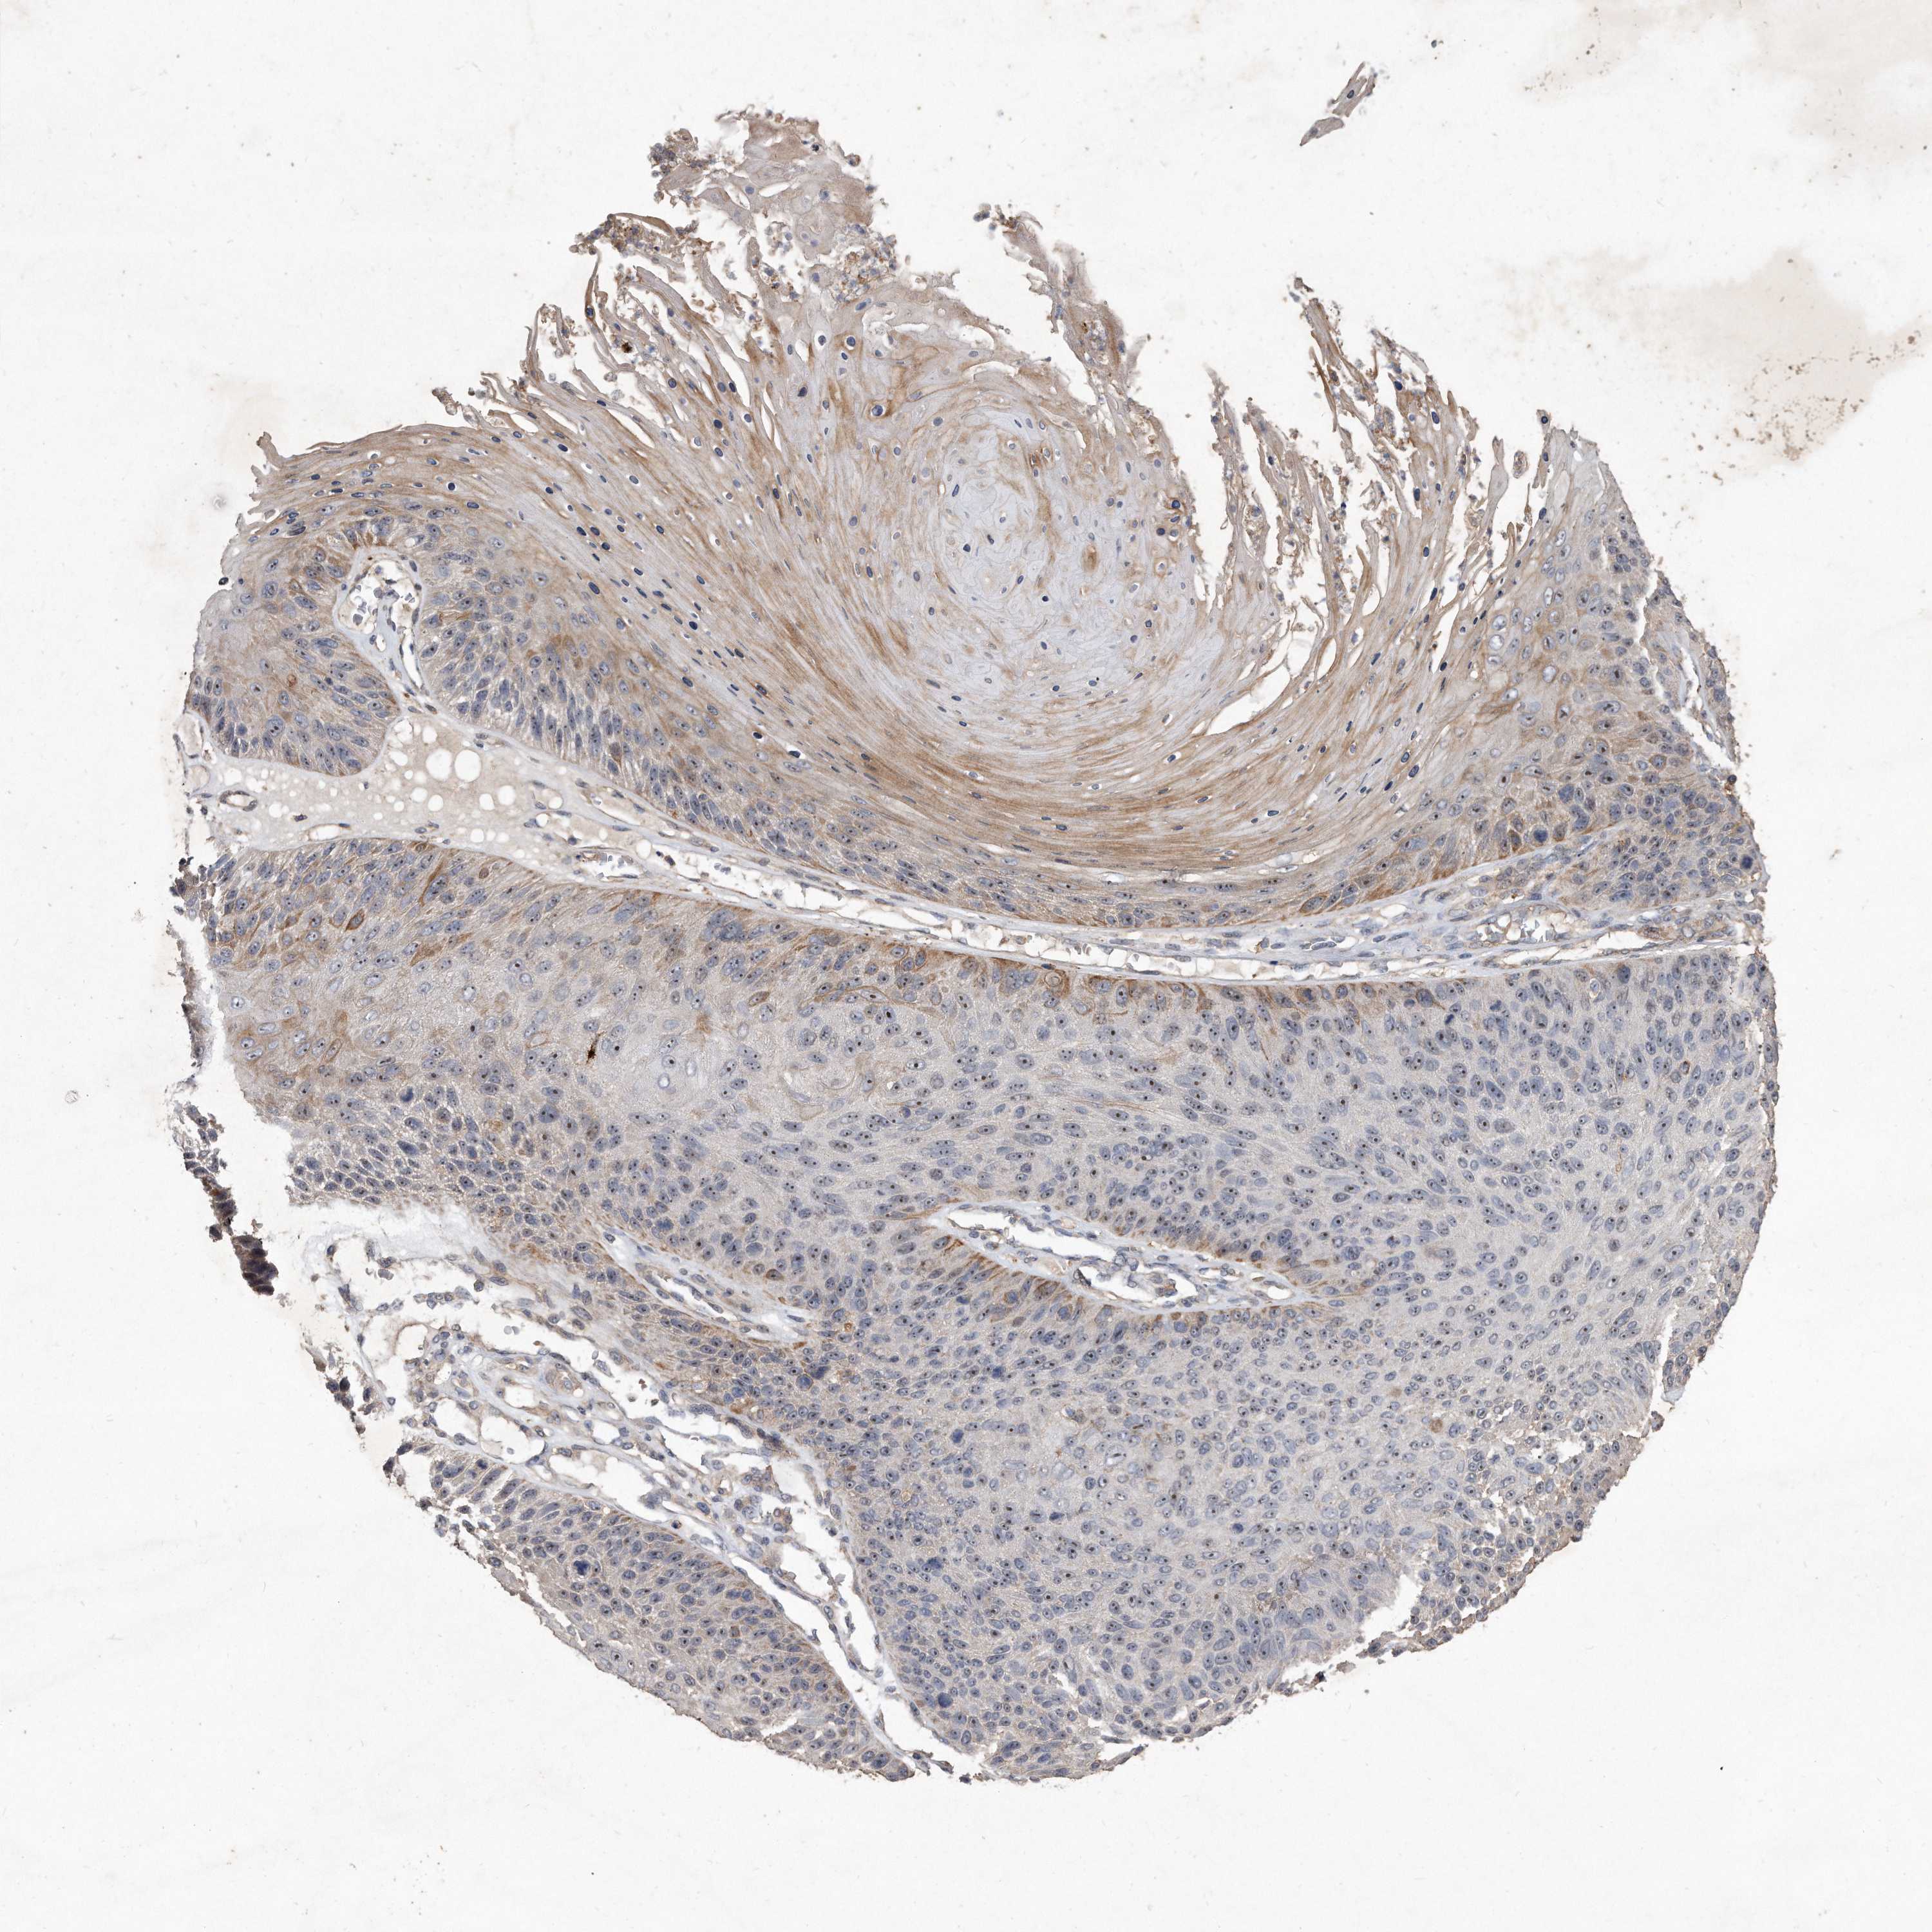

SKIN CANCER - Protein expressioni

A mouse-over function shows sample information and annotation data. Click on an image to view it in a full screen mode. Samples can be filtered based on level of antibody staining by selecting one or several of the following categories: high, medium, low and not detected. The assay and annotation is described here.

Each image is clickable and will lead to virtual microscopy that enables deeper exploration of all samples and also displays staining intensity scores, fraction scores and subcellular localization as well as patient and tissue information for each sample.

Antibody HPA029889

Squamous cell carcinoma, NOS